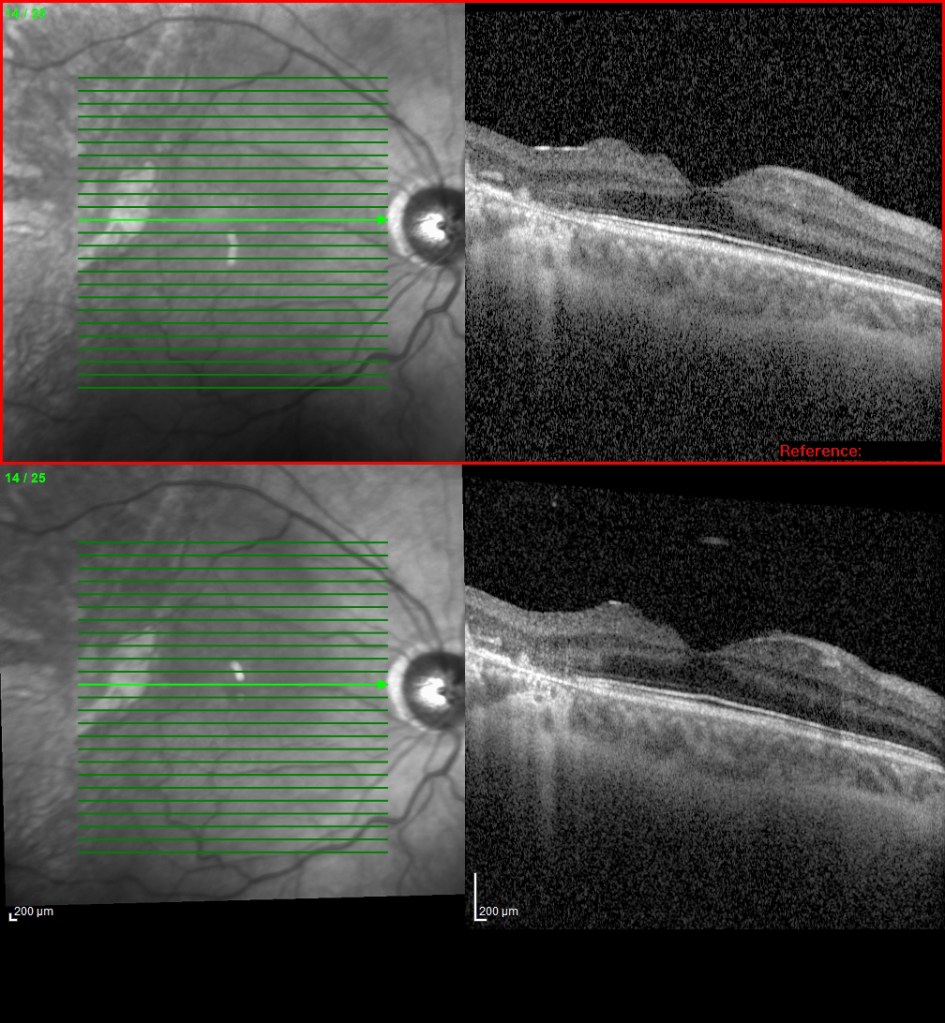

La OCT de la zona valvulada y las OCTs retinianas previas y en hipotonía:

Y por último las BMUs previas y en estado de hipotonía, donde se puede apreciar perfectamente un cambio en las medidas de todos los parámetros registrados: cámara anterior, distancia ángulo-ángulo y distancia cuerpo ciliar-cuerpo ciliar. Debido a los cambios producidos en las curvaturas corneales por las cirugías y por el cambio de medidas en las estructuras internas, se registró una disminución aproximada de 1.5 dp en la refracción (hipermetropización) del preoperatorio al postoperatorio.